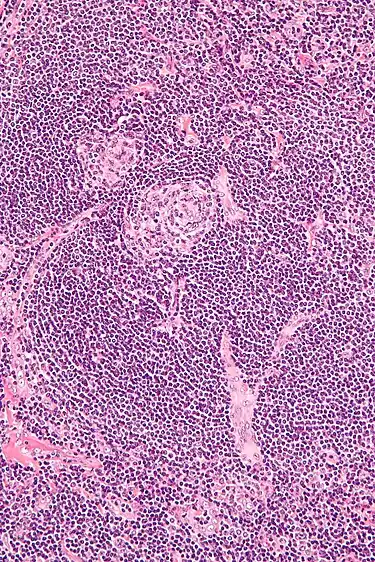

| Micrograph of lymph node biopsy demonstrating hyaline vascular features consistent with Castleman disease | |

Appearance of hyaline vascular type Castleman's disease (histology)

The microscopic appearance (histology) of biopsied tissue from an enlarged lymph node must demonstrate a constellation of features consistent with Castleman disease. There are three patterns of characteristic histologic features associated with UCD:[6]

- Hyaline vascular - regressed germinal centers, follicular dendritic cell prominence or displasia, hypervascularity in interfollicular regions, sclerotic vessels, prominent mantle zones with an “onion-skin” appearance.

- Plasmacytic – increased number of follicles with large hyperplastic germinal centers and sheetlike plasmacytosis (increased number plasma cells).

- Mixed - features of both hyaline vascular and plasmacytic patterns

UCD most commonly demonstrates hyaline vascular features; however, plasmacytic features or a mixture of both hyaline vascular and plasmacytic features may also be seen in UCD lymph nodes.[4] The clinical utility of subtyping Castleman disease by histologic features is uncertain, as histologic subtypes do not consistently predict disease severity or treatment response.[6]